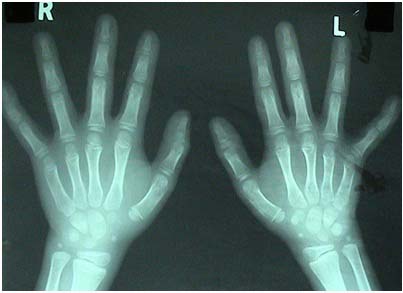

April 2004 -X-ray of the wrist joint showed 7 carpal bones

After the treatment:

August 2004